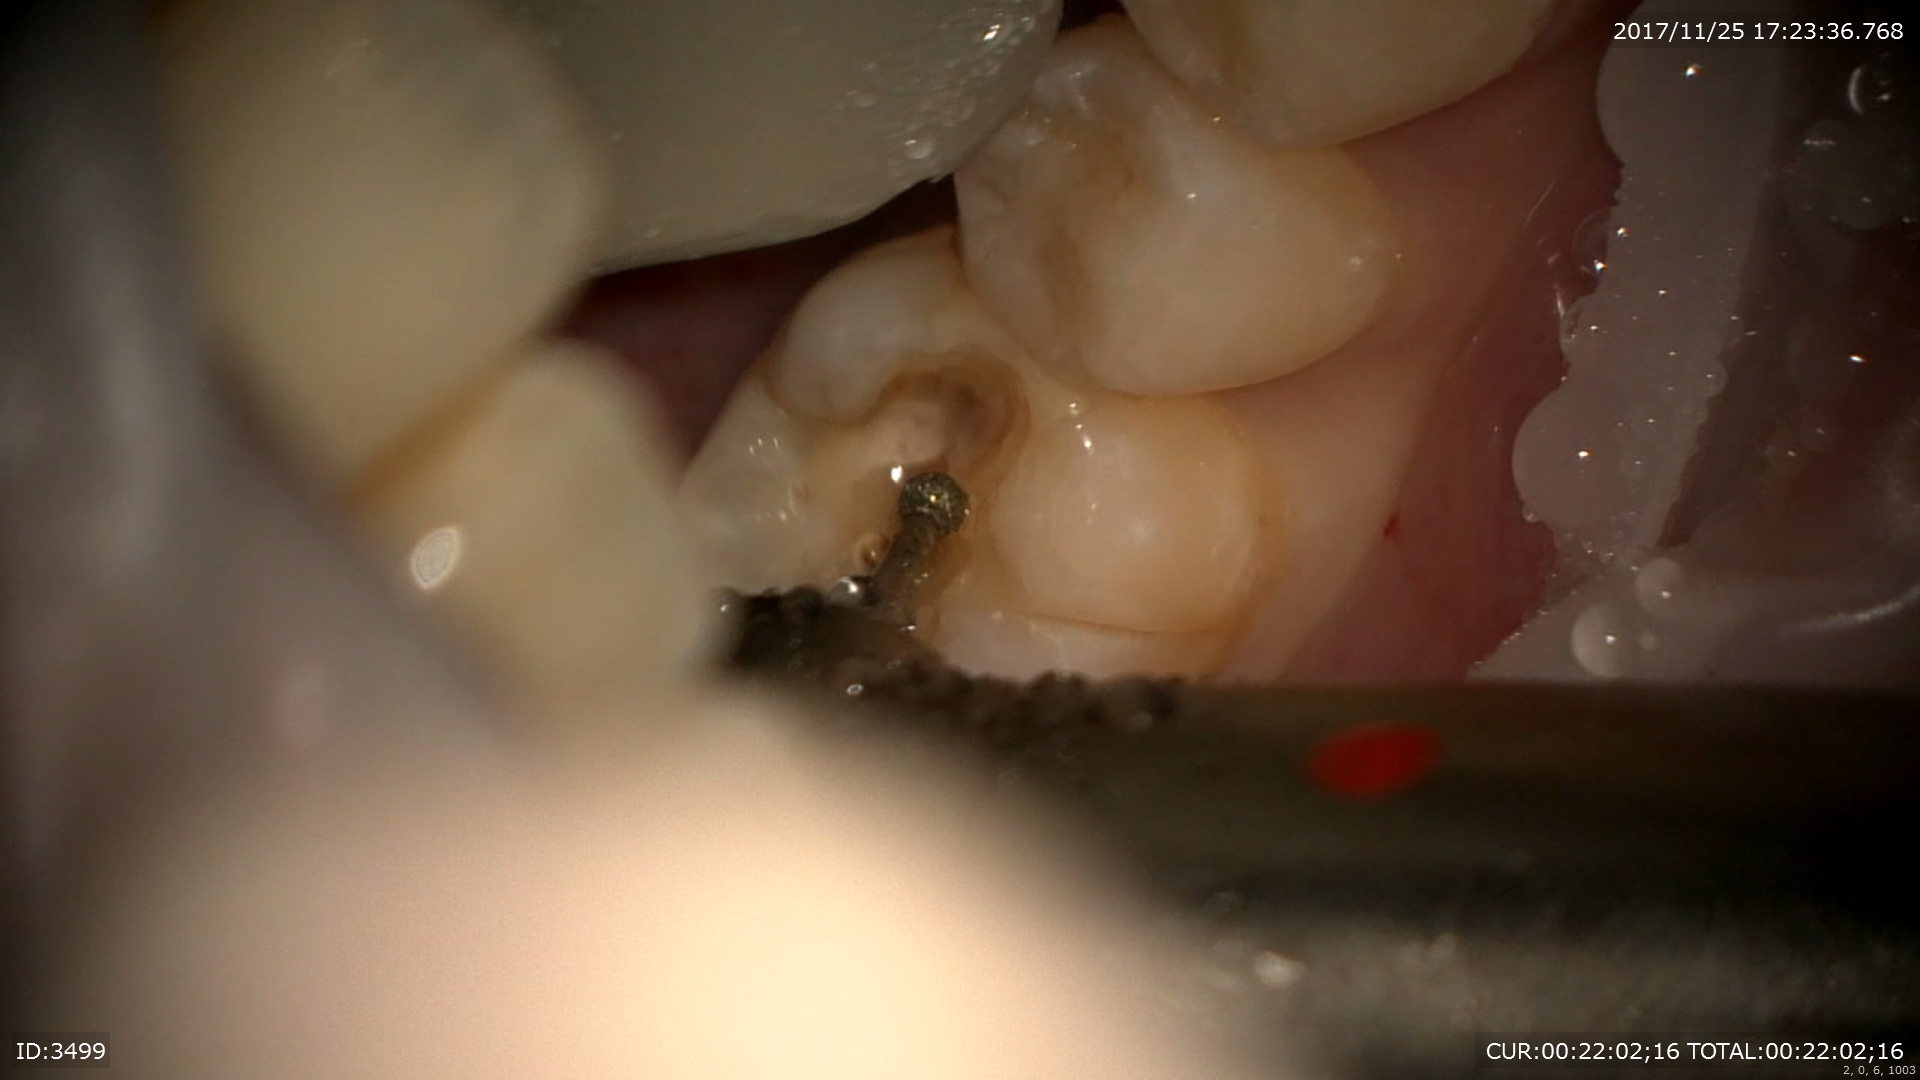

ん?歯髄から結石が!!これもマイクロエキスカで丁寧に取ります。

ん?近心根の中に2根(珍しい)1つは分岐部へ。

非常に珍しいケース。近心の根管の中に分岐部があり根管がご覧の様に縦に並んでいました。根管の形態はご覧の様に様々。だから時間と精密さが求められます。